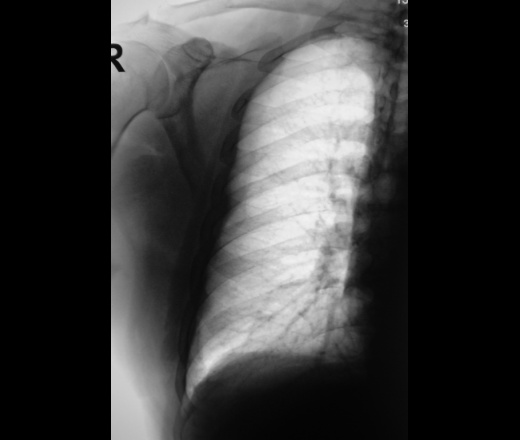

Медицина и диагностика: Аномалии ребер на рентгене